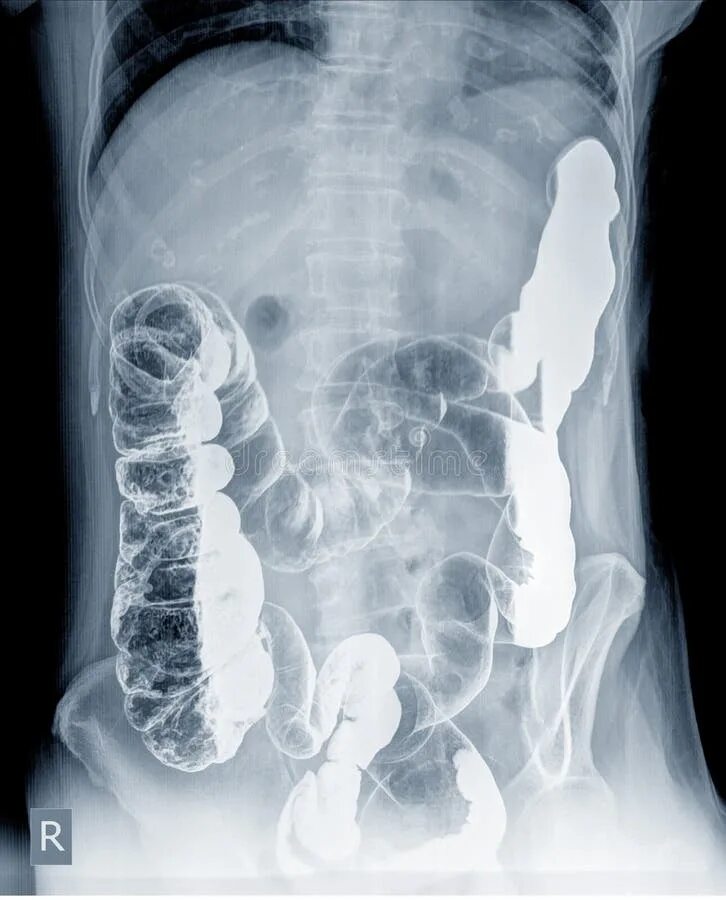

Долихоколон симптомы у взрослых